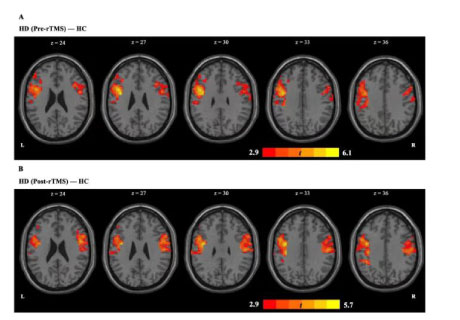

背景介紹海洛因成癮的定義為強迫性海洛因尋求和消費行為,盡管意識到嚴重的負面后果,可導致嚴重的社會和個人問題,如個人發病率、經濟損失、公共衛生危機和過度誘導的死亡率(Kolodny等,2015)。針對左側背外側前額..